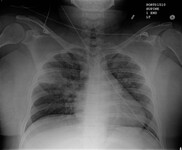

Chest x-ray showing left hilar carcinoma (arrow)

From: E. Dick, Student BMJ. 2000;8:358-360